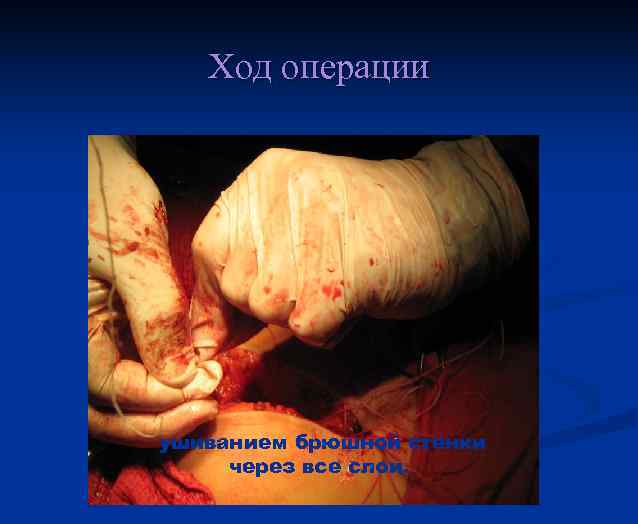

Ход операции ушиванием брюшной стенки через все слои.